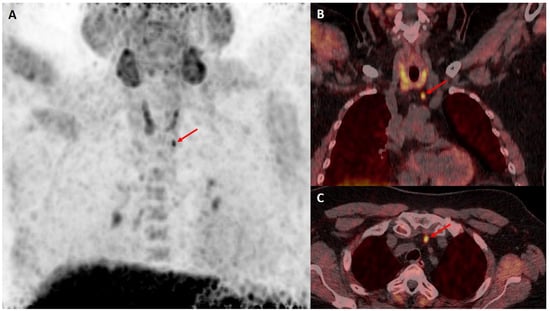

- Seyedinia, S.S.; Mirshahvalad, S.A.; Schweighofer-Zwink, G.; Hehenwarter, L.; Rendl, G.; Pirich, C.; Beheshti, M. Evolving Role of [18F]Flurocholine PET/CT in Assessing Primary Hyperparathyroidism: Can It Be Considered the First-Line Functional Imaging Approach? J. Clin. Med. 2023, 12, 812. [Google Scholar] [CrossRef]